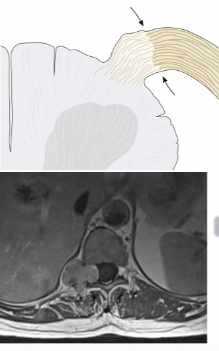

Imagem em halter (porque passa pelo forame de conjugação, e o dilata)